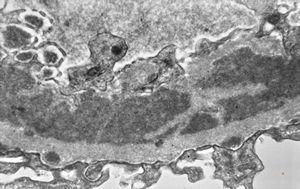

F,14y. | Alport syndrome - split and laminated, thick/thin basement membranes